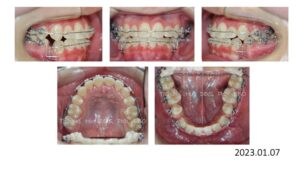

13歳の女の子、反対咬合と叢生を主訴に来院されました。

チンキャップで下顎の成長抑制を行いつつ、上顎両側5番、下顎両側4番を抜歯し、上下顎にブラケットを付け、

下顎前歯部をリトラクションし、反対咬合を改善し、ここから細かな調整に入ります。

治療が終わりました。

動的治療期間は 1年 9か月です。